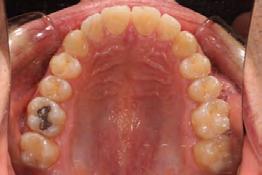

Patients often present to our practices with dental relapse of previous orthodontic treatment. Many times, the underlying skeletal and/or functional problems leading to the malocclusion were not addressed, causing the teeth to revert to their initial positions, even with good retainer wear. This patient presented with a severe lateral open bite and complained of problems chewing on his right side.

Previous orthodontic treatment with fixed orthodontics appliances and vertical elastics proved to be unstable. We recommended a treatment plan with surgically assisted rapid palatal expansion (SARPE)[1] to correct the skeletal maxillary constriction and provide more tongue space, followed by surgically facilitated orthodontic therapy (SFOT),[2,3] with myofunctional therapy to address the lateral tongue thrust most likely contributing to relapse.[4,5,6]

Clinical evaluation showed a mild Class III skeletal pattern with a constricted maxilla, mildly dolichofacial and straight

profile (Figure 1). Full adult dentition was present with all third molars extracted. Maxillary and mandibular incisors were normoclined. The maxillary midline coincided with the facial midline, and the mandibular midline was 2 mm to the right of the facial midline. There was a 2 mm to 5 mm lateral open bite on the right side from the second molar to the lateral incisor, and the maxillary occlusal plane was canted to the left of the interpupillary line. A lateral tongue thrust into the open bite was noted on swallow.

The right side was in posterior crossbite and there was an edge-to-edge anterior bite with wear on the maxillary central incisors. Mild gingival recession was noted, but soft tissue was generally within normal limits. CBCT analysis found no radiographic evidence of osteoarthritis in the TMJ joints, nor osseous or apical pathology involving the maxillary or mandibular teeth. His airway was not constricted. Initial report from the myofunctional therapist indicated that the patient never developed a mature swallow sequence and had a bilateral posterior tongue thrust.

Figure 1. Initial records.